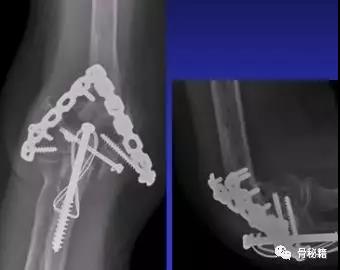

适当的固定技术原则

1、最大限度地固定远端碎片2、确保远端节段的所有固定有助于提高髁间水平的稳定性3、不建议使用三分之一管型板,因为它们太弱的并易于断裂,尤其是在粉碎干骺端

5、解剖锁定钢板板通过卓越的生物力学特性提供更好的临床疗效

6、良好的固定需要两个板,平行or垂直?在肱骨远端骨折中,一块钢板通常不足以保证良好的稳定性,而在其他骨折(例如,胫骨近端和股骨远端)中,LCP的引入消除了对双柱固定的需要。应谨慎使用单侧钢板板,仅在单柱损伤的情况下可以应用。

7、钢板如何搭配?迄今为止,通常使用前两种钢板的固定。AO推荐在治疗中应用垂直钢板。然而,这种方法受到了广泛的批评 - 主要是因为通过后外侧板难以获得足够的螺钉数量和前后方向的长度的螺钉固定。与垂直钢板相比,平行板配置似乎提供了更好的生物力学性能。实在不行的时候再用三钢板技术

固定的八个细节:1、每个螺钉都应该经过钢板固定2、每个螺钉固定骨折块的螺钉,在他的对侧应该也有一个钢板的把持3、在远端一定要打满螺钉4、每个螺钉要尽可能的长5、每个螺钉需要尽量的对关节面的骨块进行固定6、螺钉应通过交叉锁定在一起,从而形成角稳定结构并将内外侧柱连接在一起7、钢板需要再髁间完成加压8、所使用的板必须足够坚固并且足够坚硬以抵抗在髁上水平处的断裂或弯曲。

实在固定不了的时候,再进行肘关节置换术肘关节又分为半肘和全肘